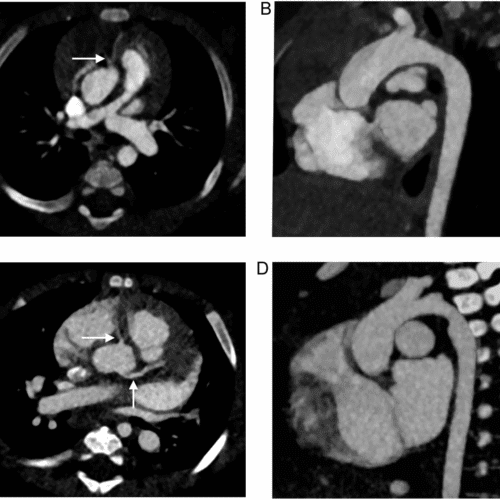

This study, published in the Journal of Medical Imaging, addresses the limitations of current evaluation practices in spectral head CT, particularly concerning iodine quantification accuracy. Traditional CT systems rely on energy-integrating detectors and dual-exposure techniques, which can increase radiation dose and introduce motion artifacts. Photon-counting detectors (PCDs) provide a promising alternative by enabling multi-energy acquisition in a single exposure with superior energy resolution. However, current evaluation standards often use cylindrical phantoms that lack anatomical realism and fail to mimic skull structures, potentially leading to overestimated system performance. To address this gap, the study compares conventional cylindrical phantoms with anatomically accurate elliptical phantoms incorporating skull-mimicking materials.

Through detailed simulations using a photon-counting CT system with cadmium telluride detectors, the researchers analyzed iodine quantification accuracy under various imaging conditions. They found that image-based material decomposition methods were highly sensitive to phantom geometry, with cylindrical phantoms showing inflated accuracy and precision. In contrast, projection-based decomposition methods were more robust, maintaining consistent performance across different phantom types. The findings highlight the critical importance of using anatomically realistic phantoms in spectral CT calibration and validation to ensure clinically relevant and accurate assessments, especially for complex head imaging.